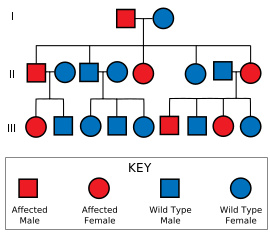

ويسبب مرضَ هنتنجتون مورث (جين) شاذ موجود على واحد من زوج من الكروموزومات يسمى الكروموزوم 4. وأي شخص يرث هذا المورث يصيبه الاضطراب، كما أن كل طفل ينجبه أي مريض مصاب بهذا المرض تكون لديه فرصة وراثة هذا المورث بنسبة 50%.

ويقدر الخبراء أنّ من بين كل مائة ألف شخص هناك عدد من الأشخاص يتراوح بين 4-7 أشخاص يحملون المورث لمرض هنتنجتون. وقد طور الباحثون وسيلة لتحديد الشخص الذي قد يحمل هذا المورث. ولكن هذا الابتكار العلمي لايزال في طور التجربة.

الوراثة